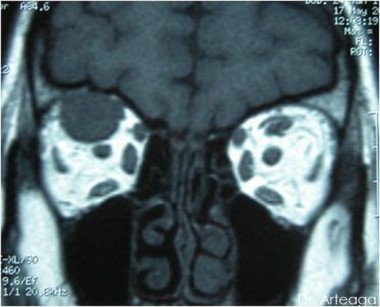

Galería de Imágenes